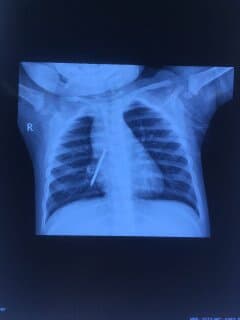

耳鼻喉科副主任医师纪尧峰主任接诊后,高度怀疑为喉裂,于是为小晨做了全面检查,结合喉镜下可见喉后部中线位粘膜或骨性裂隙,喉后部粘膜缺损,环状软骨后部出现裂隙,由于Ⅰ型常因声门后部的黏膜脱垂将黏膜裂隙掩盖而漏诊,在与家长沟通同意后,进行全麻支撑喉镜显微下以探针拨开脱垂黏膜,确诊为先天性喉裂。

术后,患儿用鼻饲1周,减少咽部活动,促进愈合。同时使用广谱抗生素预防感染,胃酸抑制剂控制胃食管反流。术后4周显微镜下观察愈合情况良好,术后18个月痊愈,恢复正常喂养。